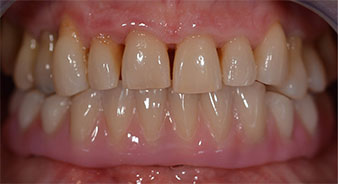

Nach der Zeit, die für die Osseointegration benötigt wird, kann die endgültige Abformung der Implantate erfolgen und entsprechend die endgültige Arbeit angefertigt werden (Abb. 19 und 20). Hier können Behandler und Patient gemeinsam entscheiden, ob diese eine Keramik- oder Kunststoffverblendung, ein Zirkon- oder Metallgerüst bekommen soll. Im vorliegenden Fall hat sich das Team um Dr. Pascu, aufgrund der unklaren Prognose der Oberkieferbezahnung und des elongierten Zahnes 24, für eine Kunststoffverblendung entschieden. Diese ist im Allgemeinen wesentlich einfacher umzustellen und der neuen Situation im Oberkiefer anzupassen.